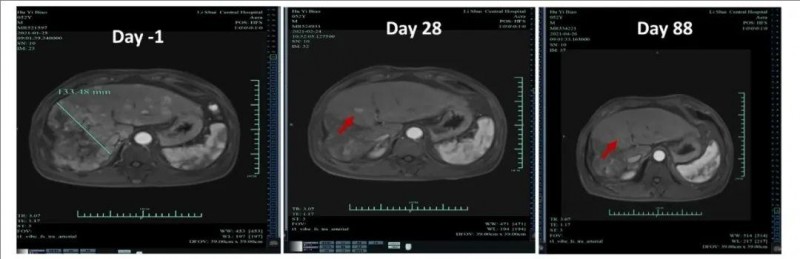

2025-11-18 16:31肝癌治疗